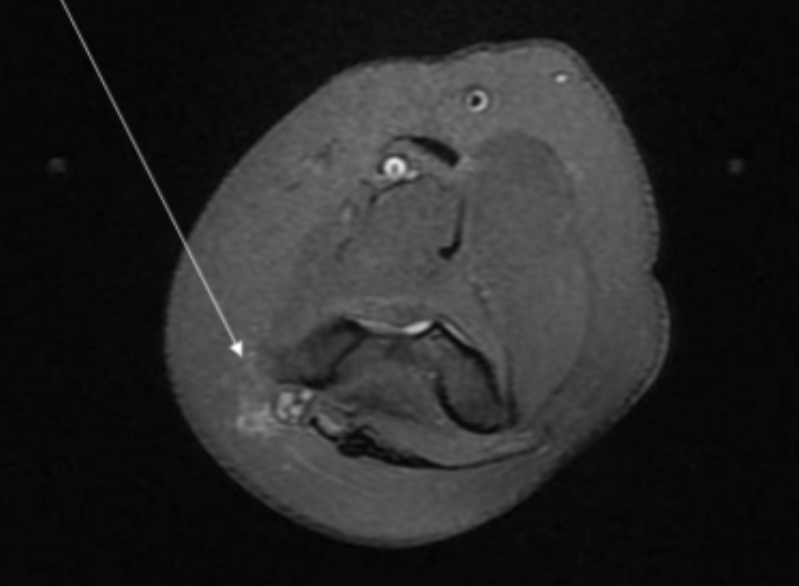

Describe the pathology indicated by the arrow (Ax PD).

Peroneal brevis tendon tear